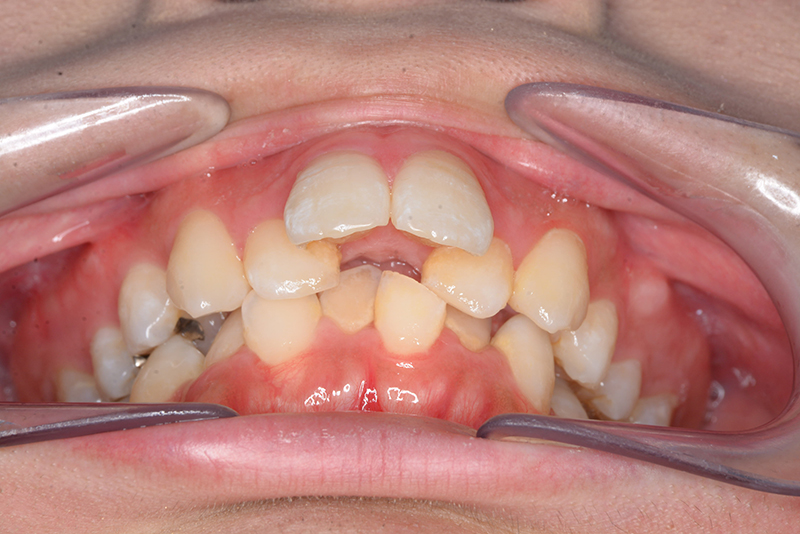

初診時

FP・IOP

口腔内所見 over jet 11.5mm、over bite 5.5mm、右側臼歯関係Full ClassⅡ級、左側end onⅡ級、上顎顎歯列はテーパー型であり、上顎中切歯は押し出されるように大きく唇側傾斜していた。下顎前歯部は叢生を呈しており、左下5は歯冠長が短く半埋伏していた。